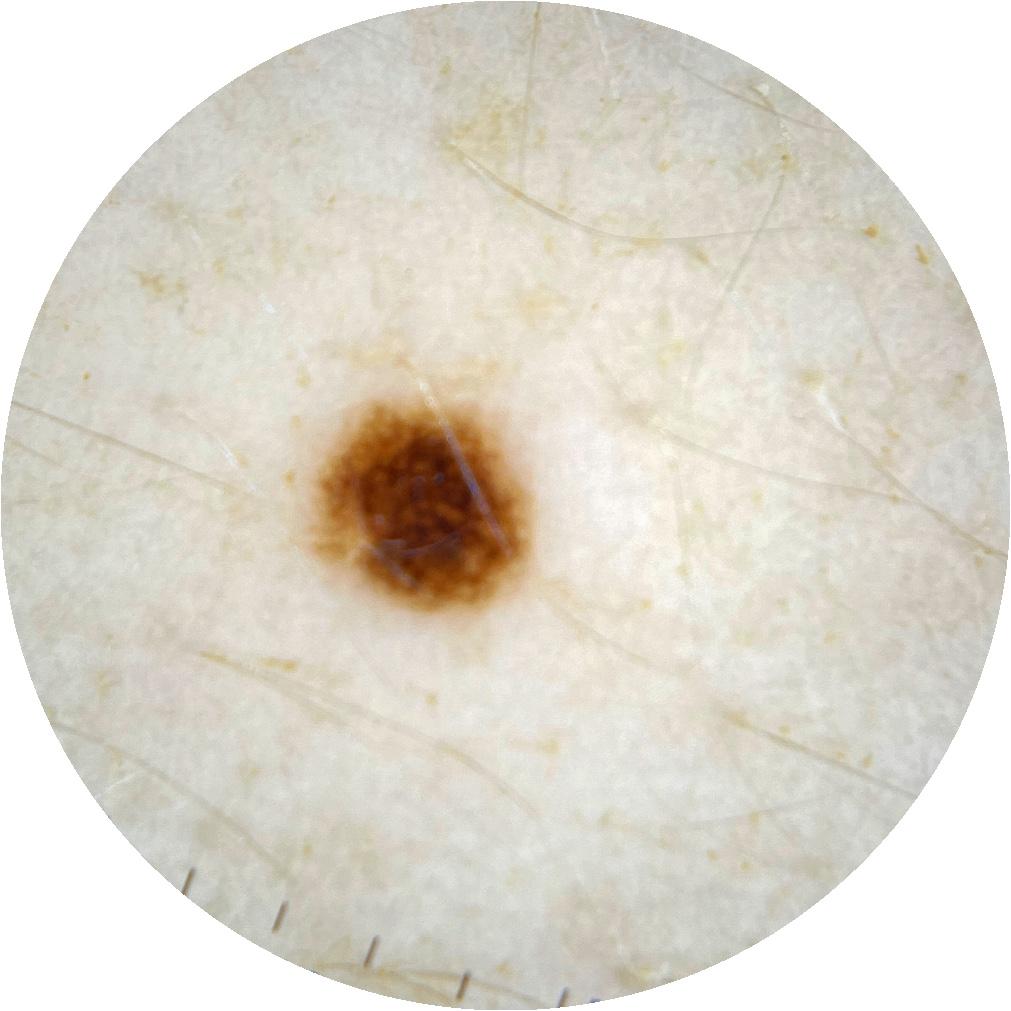

ISIC_0301375

1986 x 1986

acquisition_day 331

age_approx 35

anatom_site_1 Trunk

anatom_site_2 Anterior trunk

anatom_site_general anterior torso

diagnosis_1 Benign

diagnosis_confirm_type single image expert consensus

image_type dermoscopic